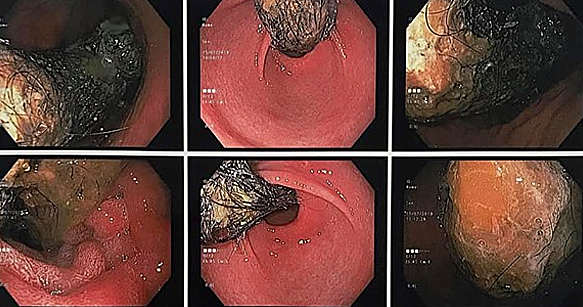

Bác sĩ Nguyễn Thị Hồng Nhân, Trưởng khoa Nhi tổng hợp, Bệnh viện Đa khoa Xanh Pôn, cho biết hình ảnh nội soi thực quản - dạ dày - tá tràng của bé cho thấy cả búi tóc trong ruột. Đuôi búi tóc vẫn còn chạy dài trong ruột non. Các bác sĩ chỉ định mổ để lấy búi tóc ra khỏi dạ dày bé.

Kết quả nội soi cho thấy búi tóc trong ruột bệnh nhi. Ảnh: Hồng Nhân.

Bé được xác định mắc hội chứng Rapunzel còn gọi là "công chúa tóc mây". Tên hội chứng được đặt tên của nàng công chúa thả tóc xuống chân tháp cho hoàng tử leo lên trong truyện cổ tích của anh em nhà Grimm.

Người mắc hội chứng này thường ăn chính tóc của mình hoặc người khác, khiến cho tóc bị rối và mắc kẹt trong dạ dày, ruột, lâu ngày gây tắc, thủng ruột. Bệnh nhân có biểu hiện đau bụng, buồn nôn, giảm cân nhanh, táo bón, tiêu chảy... Nặng hơn, ruột bị đâm thủng sẽ gây ra nhiễm trùng huyết. Khoảng 4% bệnh nhân Rapunzel tử vong.